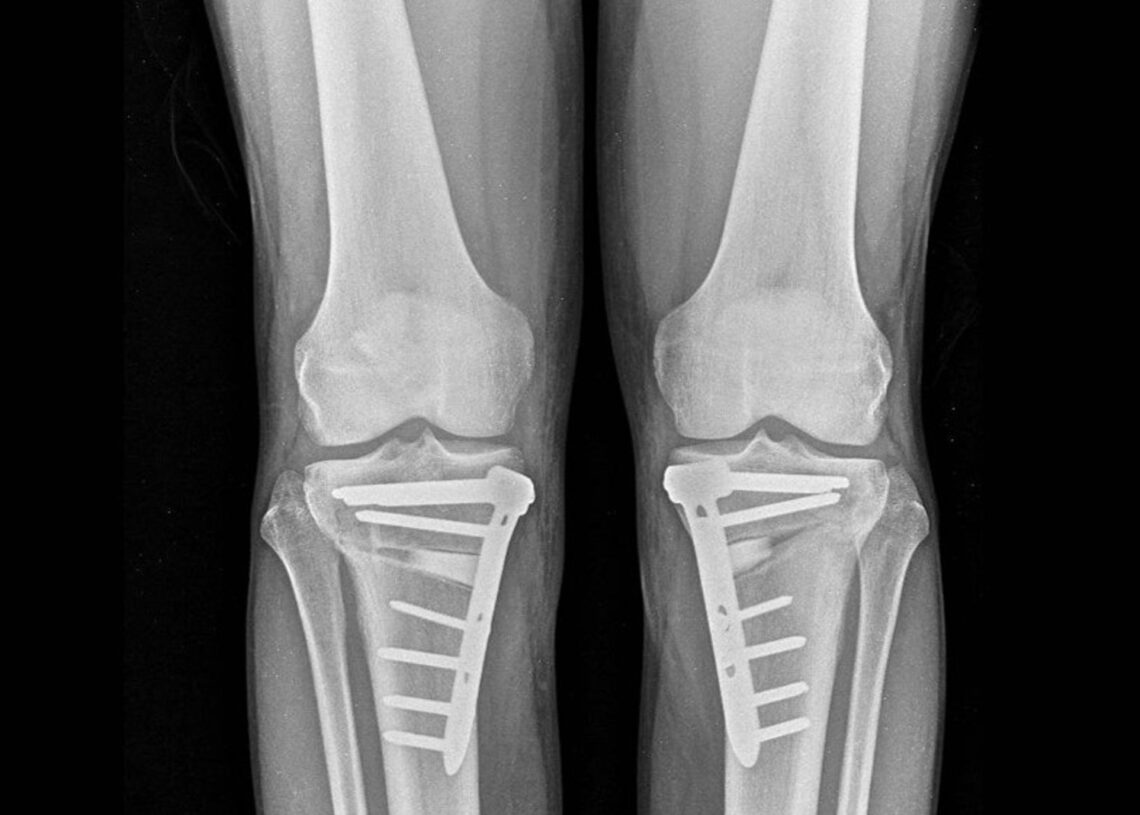

La técnica de la osteotomía se lleva a cabo mediante un corte preciso en el hueso (tibia o fémur) para ajustar la carga en la pierna, redistribuyendo el peso sobre la articulación y mitigando el dolor. El doctor Arnal ha destacado la transformación de esta técnica debido a avances como la planificación digital tridimensional y nuevos sistemas de fijación e implantes. “Hoy podemos planificar en el ordenador la corrección exacta y, si lo deseamos, imprimir en 3D guías quirúrgicas personalizadas. Además, los nuevos sistemas de fijación permiten que el paciente empiece a apoyar la pierna a las 24 horas”, explicó.